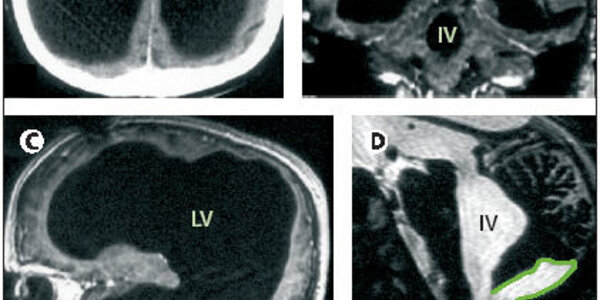

The Mystery Of The Man With The Tiny Brain

You don't need a big brain, or a high IQ, to have a comfortable life and a good family. Witness the case of this French civil servant, written about by Dr. Lionel Fuillet in The Lancet. At age six months he was treated for hydrocephalus (water on the brain) with a shunt in his head to drain away the fluid. At age 14 he complained of unsteadiness and left leg weakness, which cleared up after the shunt was adjusted. Beyond that his neurological development and medical history were normal. At age 44 the leg weakness returned and he was treated by Dr. Feuillet and colleagues of the Hôpital de…